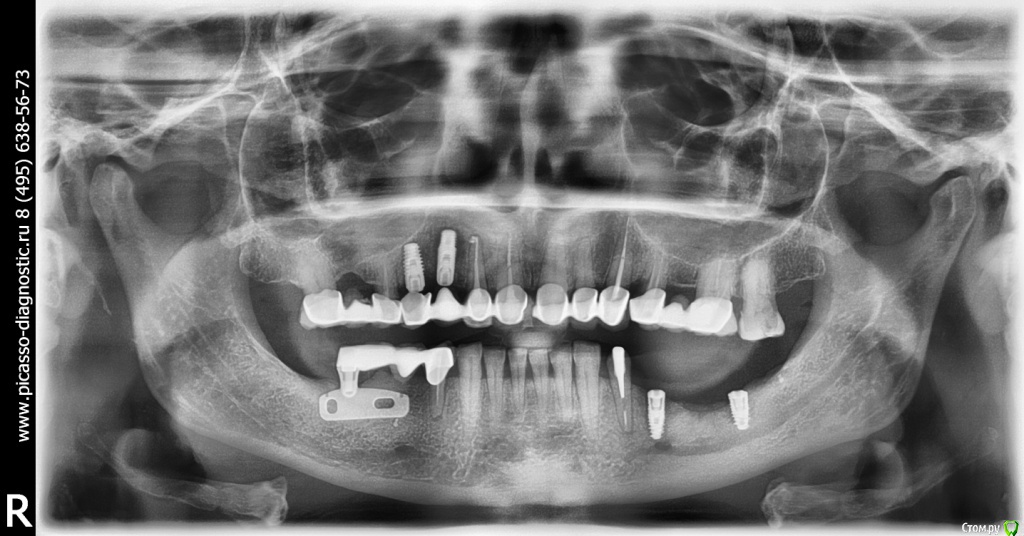

Tatyana-P Опубликовано 11 апреля, 2016 Поделиться Опубликовано 11 апреля, 2016 Добрый день!Прошу проконсультировать по моей проблеме, так как мнения двух докторов по моей ситуации разделились. У меня установлены 3 месяца назад нижние 2 импланта на проблемную челюсть (на этом месте пол года назад был удален имплант "очень старого поколения", потеря кости была большая, но решили, что можно обойтись без наращивания). Верхние импланты установлены 1 мес. назад, сними, как говорят, проблем нет. На данный момент картина такая (снимок приложен).Проблема с нижними имплантами - один доктор считает, что их надо удалять, так как они не приживаются, второй считает, что ситуация не идеальная, но не критическая, приемлемая, что нужно подождать еще месяц и посмотреть, какая будет динамика. Пожалуйста, подскажите, есть ли необходимость в изъятии, или можно как-то еще побороться?С благодарностью и уважением, Татьяна. Ссылка на комментарий

red_butler Опубликовано 11 апреля, 2016 Поделиться Опубликовано 11 апреля, 2016 Дальний точно удалять, а в позиции 3.5 нужно смотреть в полости рта Ссылка на комментарий